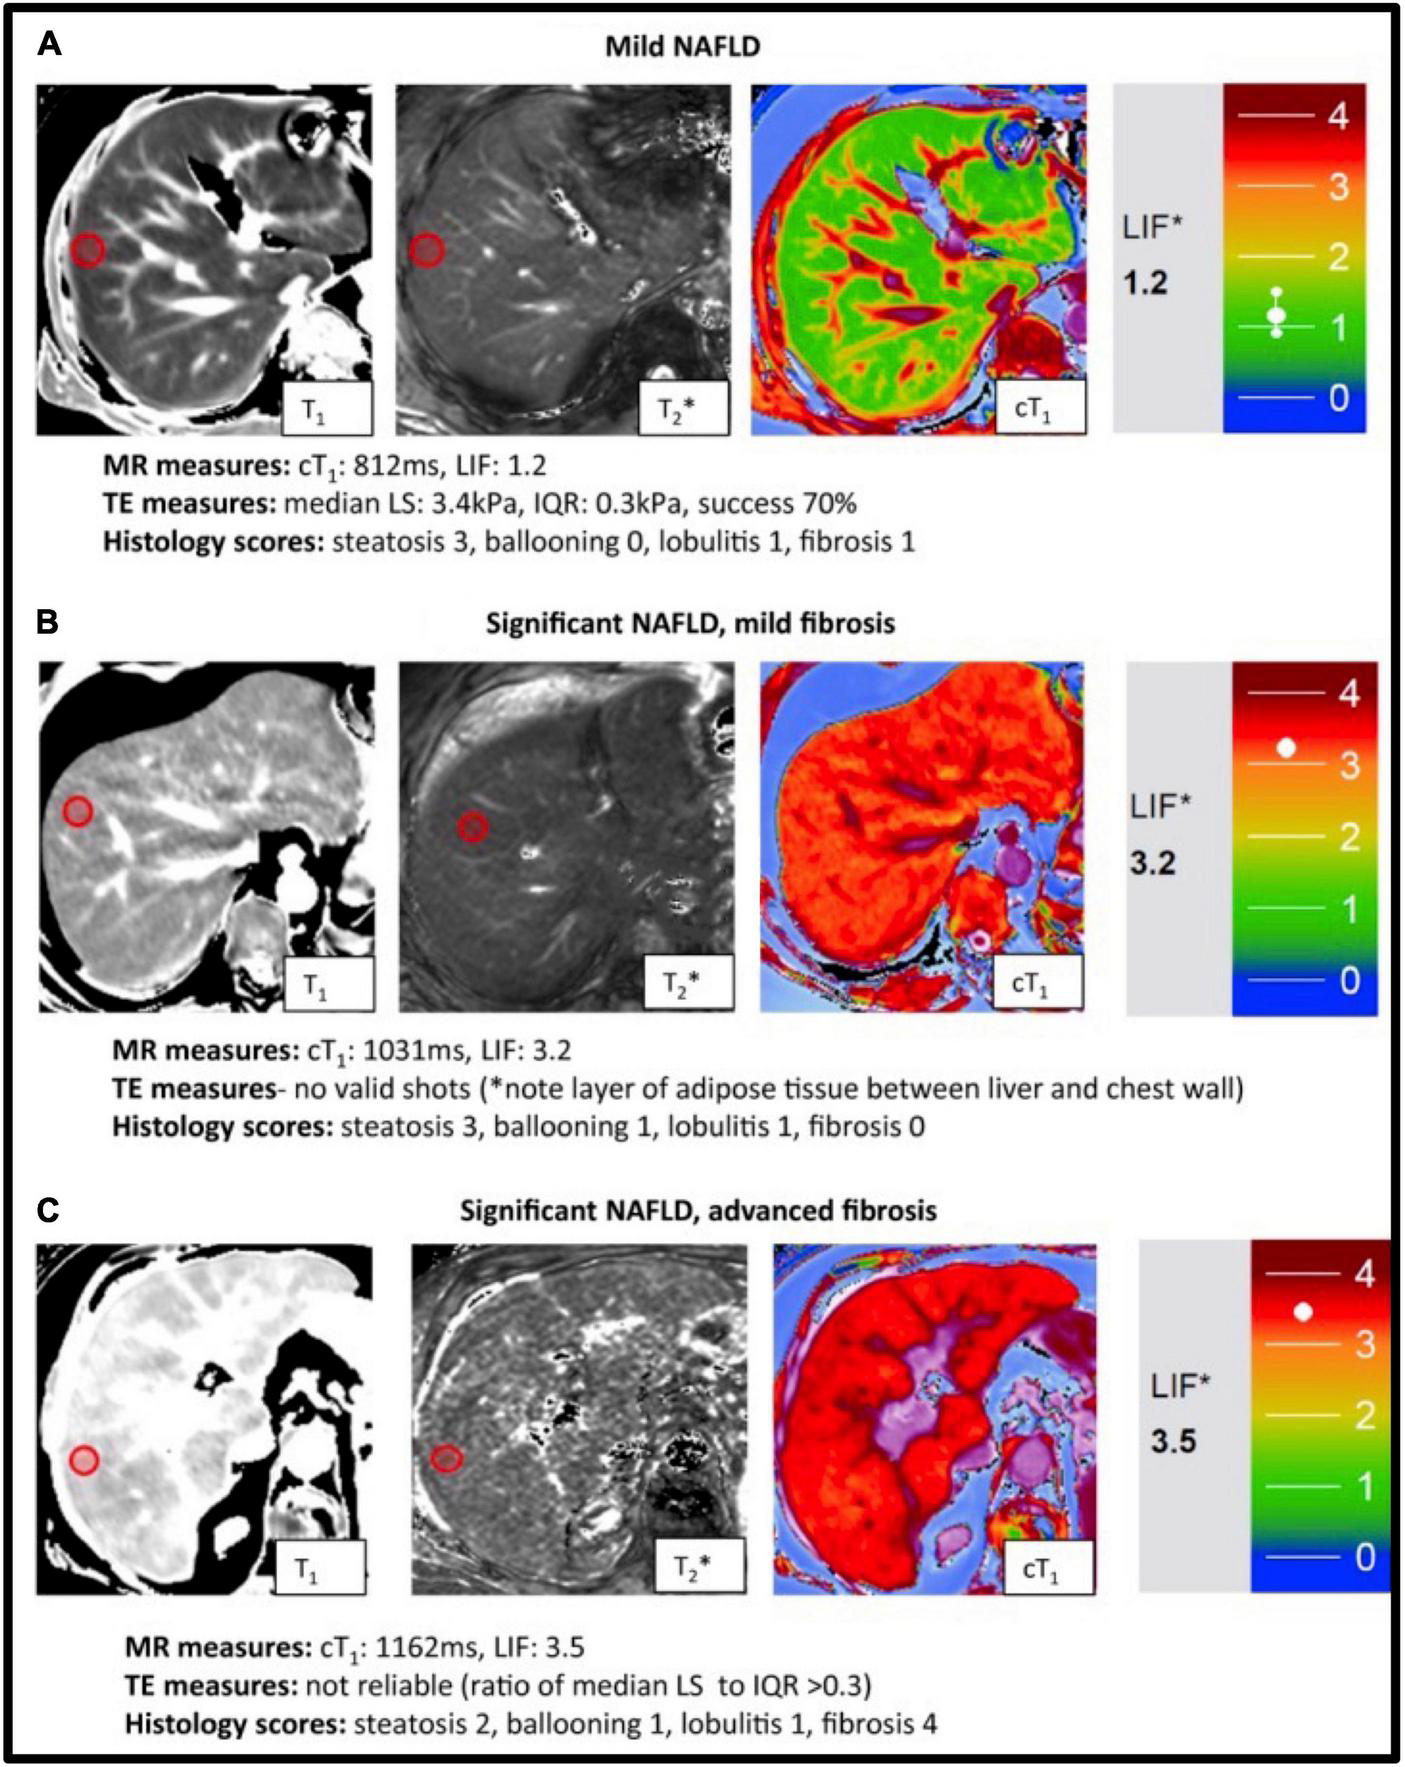

FIGURE 7

Representative magnetic resonance data with the corresponding transient elastography (TE) and histology data from patients with known or suspected non-alcoholic fatty liver disease NAFLD. T1, T2* mapping values were used to derive the calculated corrected T1 maps (cT1) maps and Liver Inflammation and Fibrosis (LIF) scores. Patients were classified based on biopsy findings, using the Fatty Liver Inhibition of Progression (FLIP) algorithm (92), as having: mild disease (A), significant disease/mild fibrosis (B) and significant disease/advanced fibrosis (C). Red circles indicate typical regions of interest. There was a significant association between histological fibrosis and MRI LIF scores. Adapted from Pavlides et al. with permission (130).

The multiparametric maps from the aforementioned approaches are obtained after pixel-wise fitting to a sequence-dependent model. However, the need of resting periods for magnetization recovery and the use of breath-holds results in low spatial resolution, limited coverage, and motion artifacts if patients are unable to hold their breath. Applications for cardiac imaging, that sought to address these issues and to enable the acquisition in a clinically-feasible scan time have also been proposed (125) (126; Figure 6A, B1, B2). Those rely on “dictionary matching.” Using this approach, a dictionary is generated which is a compendium of possible signal evolutions for a set of combinations of parameters of interest (such as T1 or T2), which can be calculated, for example with Bloch simulations (118) or the Extended Phase Graph (127) formalism. The “multi-parametric MR signal” of every pixel is then compared against all entries included in the dictionary by pattern matching (e.g., dot product or least square), to estimate the parameter combination that best represents the measured signal evolution. Dictionaries can also be employed to predict the signal evolution of the transient state; as proposed in MRF. There exist also several examples of multiparametric approaches which were proposed for liver imaging, including water/fat-separated T1 mapping (MP-Dixon-GRASP) (128) along with PDFF imaging and water-specific T1 mapping [T1(Water)] (PROFIT1) (113). An alternative approach has been proposed by Pavlides et al. This includes T1 mapping for fibrosis/inflammation imaging and T2* mapping for liver iron quantification. The T1 measurements of this method are adjusted for the iron level, as high iron levels in the presence of fibrosis can lead to “pseudo-normal” T1 values. This was achieved by integrating the results from shortened-MOLLI T1 maps and T2^* maps in an algorithm that allows to correct for the bias introduced by elevated iron in the T1 measurements, yielding iron−corrected T1 maps (110, 129). In total, seventy−one patients with suspected NAFLD were recruited within 1 month of liver biopsy and the performance of multiparametric magnetic resonance for the assessment of NASH and fibrosis was evaluated using histology as reference standard (130; Figure 7). Fibrosis stage as analysed on biopsy correlated with MRI-estimated inflammation and fibrosis (rs = 0.51, P < 0.0001). The AUC using this multi-parametric approach for the diagnosis of cirrhosis was 0.85 (95% CI: 0.76–0.95; P = 0.0002) and for the diagnosis of mild vs significant NAFLD was 0.89 (95% CI: 0.80–0.98%; P < 0.0001). This prospective pilot study demonstrated the potential of multiparametric QMRI to assess the overall disease severity in patients with NAFLD.